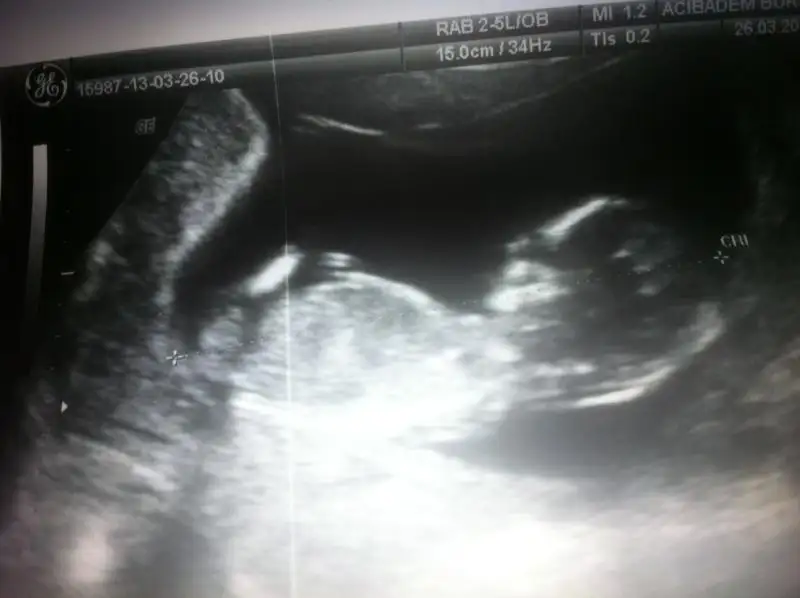

dr soylemeden siz gorun genital nub teorisi ( bebegin cinsiyeti)

canim dr un kiz demis ama ilki kiz gibi ikinci resimm ise bariz erkekk